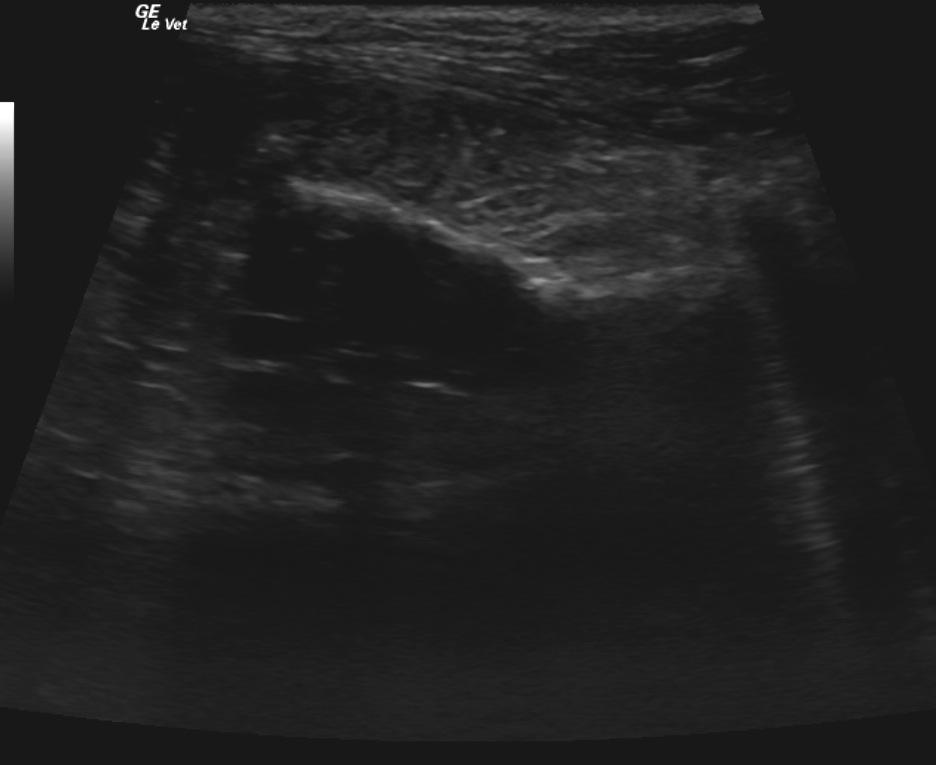

Video 1: Gastric dilation with a 5cm highly irregular shadowing foreign material that entered the duodenum and continued into distal small intestines. Video 2: Aggressive accordion shape and an ill defined intestine and mesentery. A minor amount of free fluid (arrow).